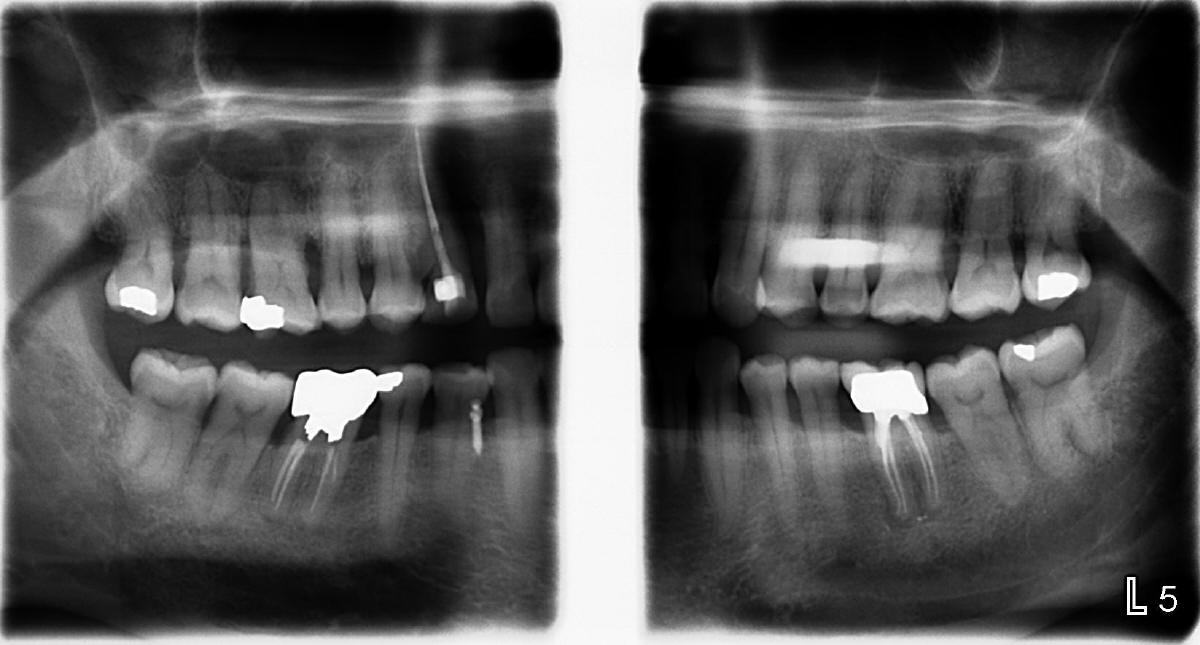

A 1.6x6 mm mini-implant was placed between #27 and 28 on 02/20/2014 (Fig.1,2). The major problem is its angulation. A 1/4 elastic cannot be placed over it. Instead a ligature wire is used to hold the elastic in place (Fig.3,4, taken 2 months later). Occlusal reduction is done (Fig.4), which alleviates the discomfort. But the extrusion is not obvious, since retraction is not 24 hours. The elastic and wire needs replacement quite often, which is not patient friendly. The extraoral Bitewing is taken 2.5 months post implantation (Fig.5). The tooth #6 has a long root. What should we do?